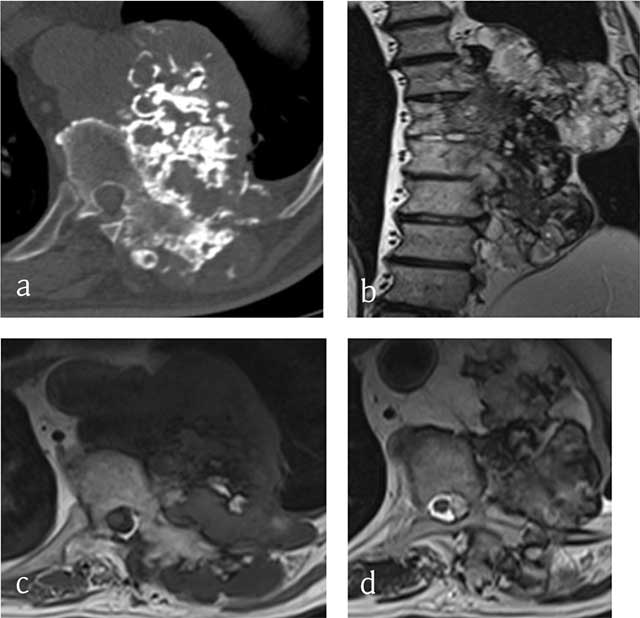

Figure 2

Chondrosarcoma of T8, T9 and T10. (a) Axial CT scan shows a large mass arising from the vertebral body with ring-and-arc calcifications. MRI (b) coronal T2-WI, (c) Axial T1-WI and (d) Axial T2-WI show a heterogenous mass consisting of lobules of intermediate signal intensity on T1-WI with residual intralesional bony trabeculae and high signal on T2-WI sourrounded by hypointense ring-and-arcs.